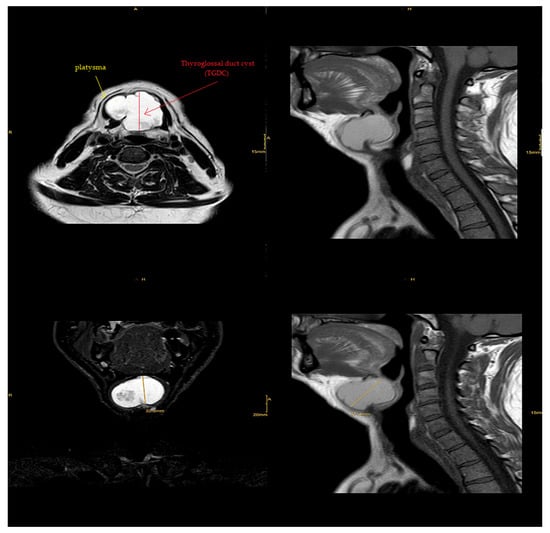

Magnetic resonance imaging (MRI) of the neck’s soft tissues (native and IV KM) diagnosed it as a suprahyoid thyroglossal cyst located posterior to the platysma, as it appeared hyperintense in T2 with isointense parts and was also isointense in T1 with an extension of approximately 0.041 m × 0.044 m × 0.033 m. There was minimal displacement of the hypopharynx and epiglottis with no evident connection to the thyroid gland or the tongue’s base. There was also discreet contrast-medium uptake of the wall and protein-rich fluid, indicating possible previous inflammation. We found no cervical lymphadenopathy, and the submandibular gland and parotid gland were inconspicuous. In the cervical spine, as shown in Figure 3, no significant degenerative changes could be identified.

Figure 3.

MRI image of the neck’s soft tissues (native and IV KM) showing suprahyoid thyroglossal cyst located posterior to the platysma.

There is a risk of infection with or without an abscess when thyroglossal fragments remain attached to the tongue’s base via the tract, which can represent the start of a thyroglossal cyst’s presentation [22]. In our patient, MRI showed signs of previous inflammation. As that could have been the cause of the cyst enlargement, we leaned toward a diagnosis of a thyroglossal cyst.

However, some of the disadvantages of ultrasound imaging (sonography) lie in the fact that it does not visualize hyoid and infrahyoid TGDCs reliably, and cannot reliably measure the base of the tongue in a suprahyoid cyst. MRI is often preferred for an athyroid cyst near the tongue’s base [24]. On T2-weighted MRI images, a typical TGDC) appears as a huge cyst with characteristic upward tapering and a hyperintense tract spreading to the tongue’s base. That was somewhat close to our patient’s MRI, which supported the preoperative diagnosis of a TGDC.

On reviewing the literature, the presence of a mass in the neck was the only evidence based on which to diagnose the condition during the examination of the case. With laboratory investigation, the final diagnosis indicated a suprahyoid thyroglossal cyst located posterior to the platysma, with an extension of approximately 0.041 m × 0.044 m × 0.033 m.